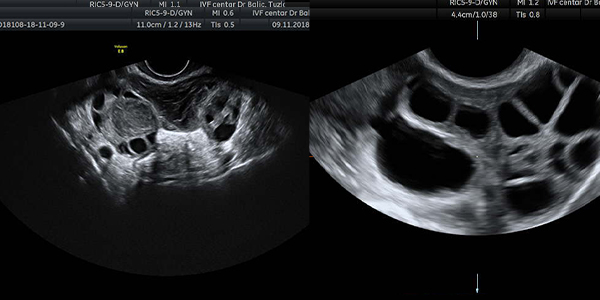

Crnobijeli ili 2D (dvodimenzionalni) ultrazvučni pregled

Ovo su standarni pregledi kojima dobijamo informacije o veličini, strukturi, obliku materice, jajnika, te o eventualnim drugim promjenama u maloj karlici žene čime vrlo brzo postavljamo dijagnozu kad je u pitanju najveći broj ginekološki oboljenja i poremećaja kao što je izostanak menstruacije, krvarenja i razni drugi menstrualni pormećaji.